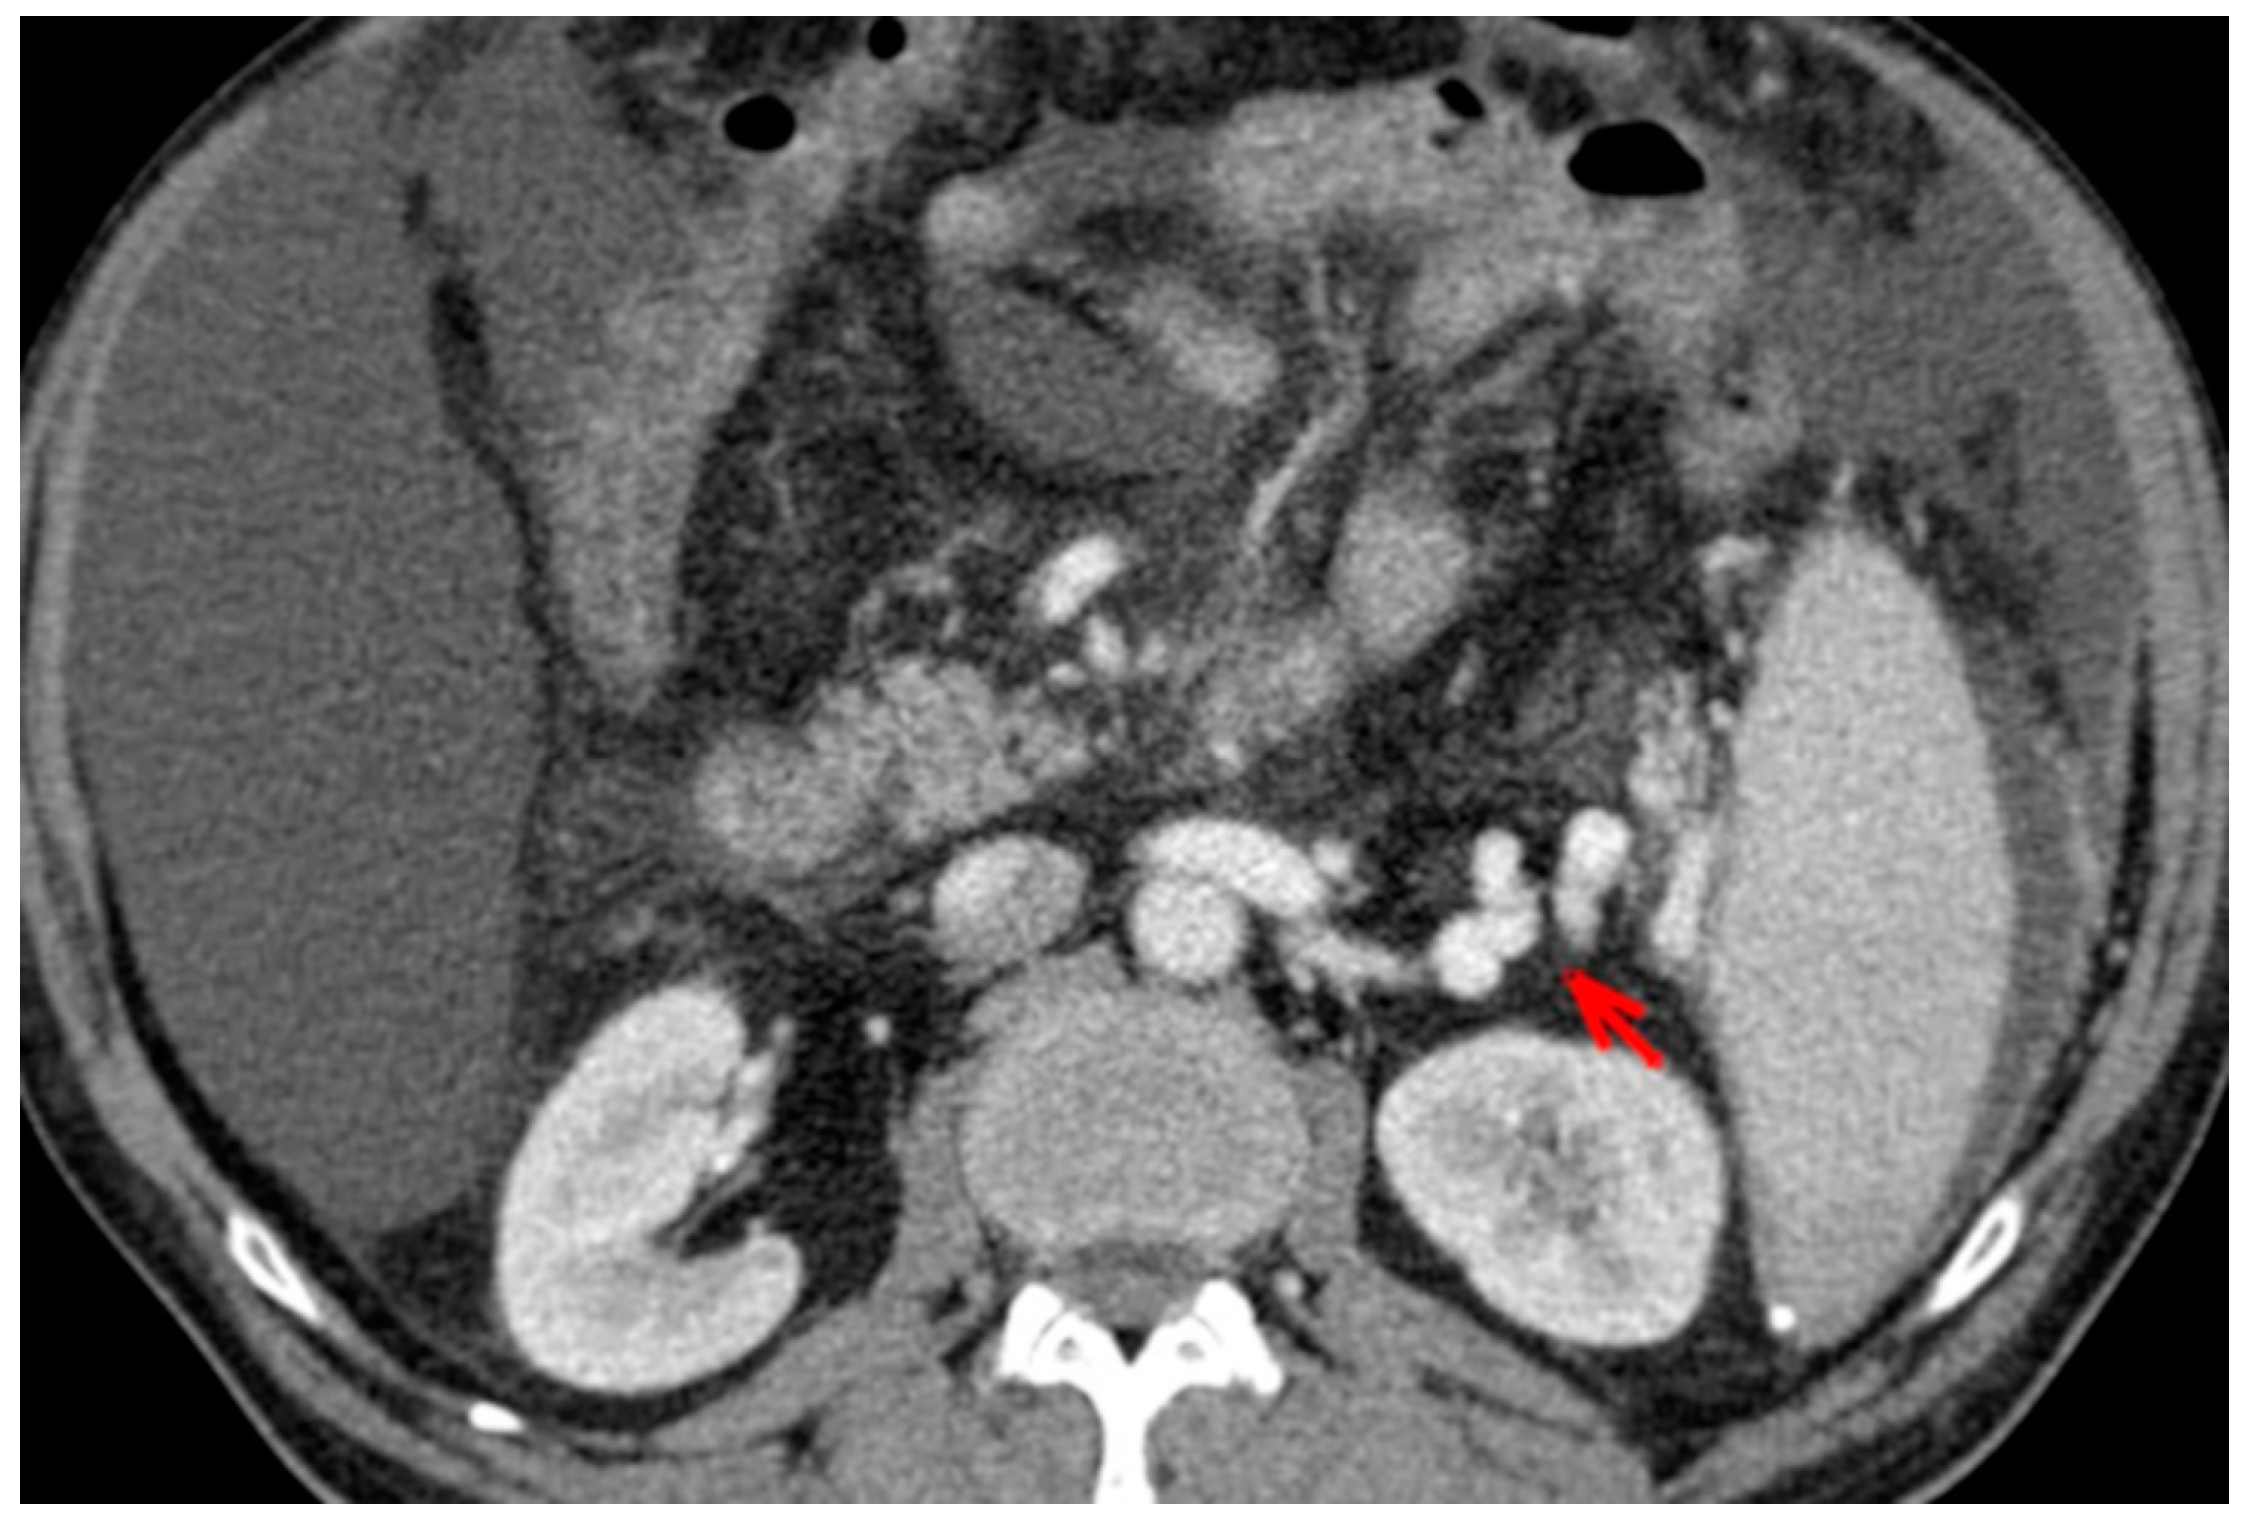

For this study, the images were retrospectively analyzed in consensus by two readers with experience in the field of abdominal imaging. The two readers assessed the following CT features: (1) The presence or absence of paraoesophageal varices and the size(mm) of the largest varix (Figure 1); (2) the presence or absence of paragastric varices and the size (mm) of the largest varix (Figure 2); (3) the largest diameter of the left gastric vein (Figure 3); (4) the presence or absence of splenorenal shunts and the size(mm) of the shunt (Figure 4); (5) the presence or absence of a repermeabilized round ligament and the size(mm) of it (Figure 5).

Figure 4. Axial contrast-enhanced CT shows spleno-renal shunt (red arrow).